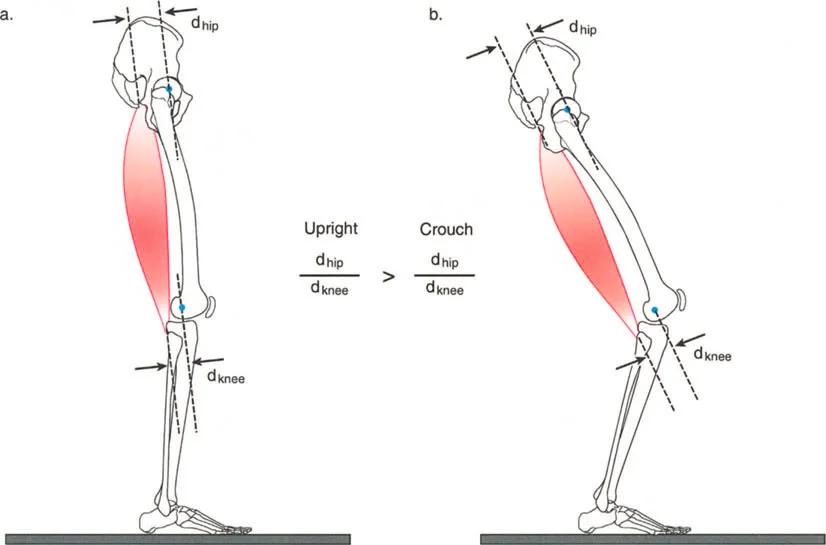

أمثلة أخرى رئيسية للتشوهات الديناميكية تشمل "الورم الفخذي المفرط" (Severe Femoral Anteversion) و "الورك الأفحج" (Coxa Vara). في كلتا هاتين الشذوذات المعمارية، يتم تقصير الطول الفيزيائي لذراع الرافعة لعضلات المبعدة (Abductor muscles) بشكل مرضي بسبب التشوه العظمي نفسه. قد تكون عضلة الألوية الوسطى (Gluteus Medius) صحية تمامًا، ومعصبة جيدًا، وقادرة على توليد قوة بيولوجية طبيعية، لكنها تعاني من خلل وظيفي سريري عميق لأن ميزتها الميكانيكية قد سُلبت بسبب الهندسة الهيكلية المتغيرة. هذه الفئة الفرعية المحددة من الأمراض تُعرف باسم "تشوه في طول ذراع الرافعة".

في حين أن التشوهات الديناميكية تُناقش غالبًا في سياق أمراض الأعصاب والعضلات لدى الأطفال، فإن المبادئ البيوميكانيكية التي تحكمها تنطبق عالميًا على إعادة بناء العظام لدى البالغين. يشمل ذلك سيناريوهات إعادة البناء المعقدة للغاية، مثل استبدال مفصل الركبة الكلي (TKR) واستبدال مفصل الورك الكلي (THR) المرتبطة بالانحرافات الشديدة خارج المفصل. إن فهم الأذرع الرافعة هو المتطلب الأساسي لإتقان هذه التقنيات المتقدمة في جراحة المفاصل وقطع العظم، وهو ما يتقنه الأستاذ الدكتور محمد هطيف في ممارسته اليومية.

بينما لا يستطيع الطب الحديث فعل الكثير لزيادة القوة البيولوجية الخام التي تولدها العضلة بشكل دائم (بخلاف العلاج الطبيعي)، يمكن غالبًا زيادة حجم العزم المؤثر على المفصل بشكل كبير ببساطة عن طريق تصحيح خلل وظيفة الذراع الرافعة جراحيًا. هذا هو جوهر النهج الذي يتبعه الأستاذ الدكتور محمد هطيف في علاج التشوهات العظمية المعقدة، حيث يركز على استعادة الميكانيكا الحيوية السليمة للجسم.